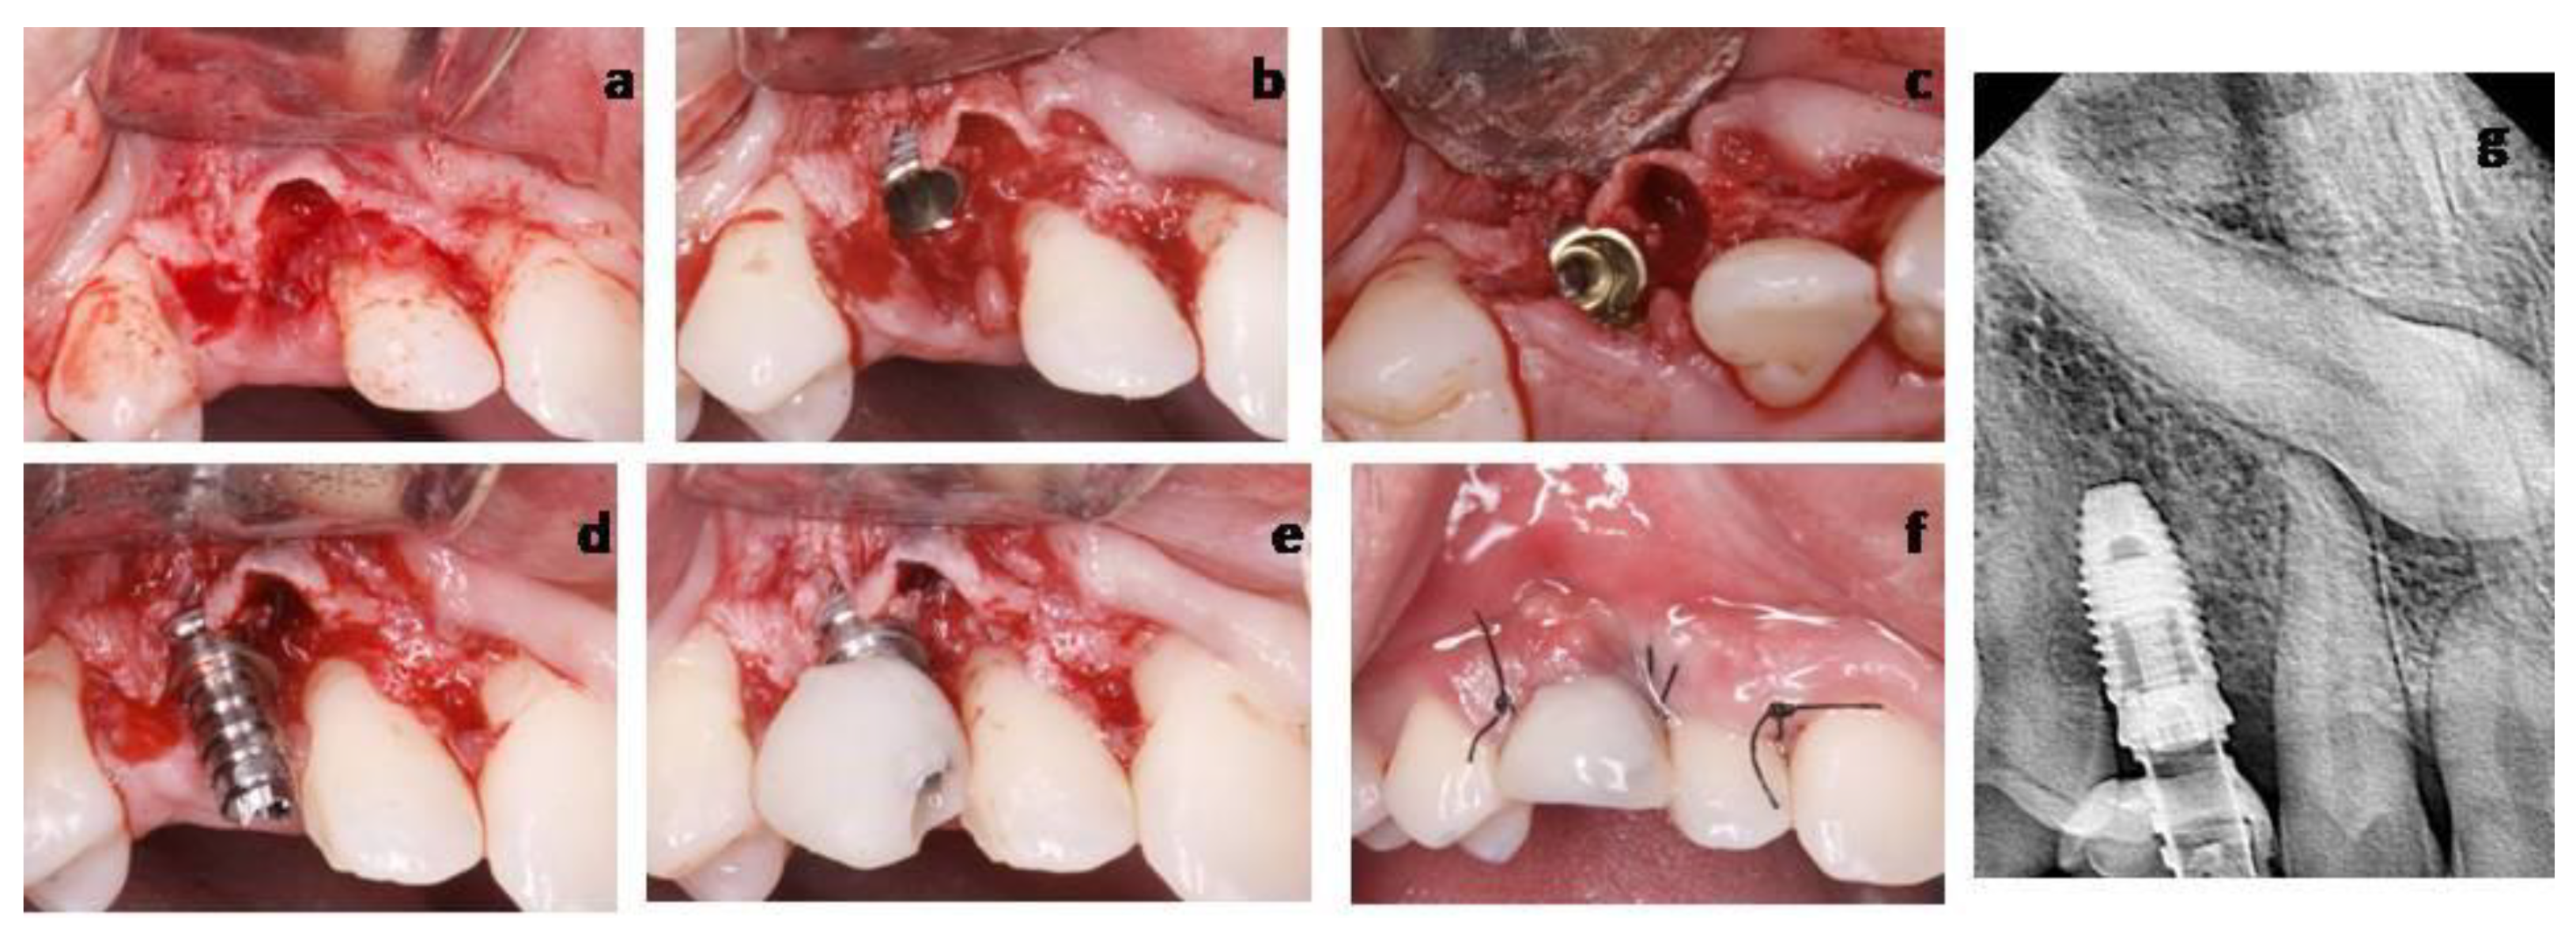

2.2.1. Case 1

2.2.2. Case 2